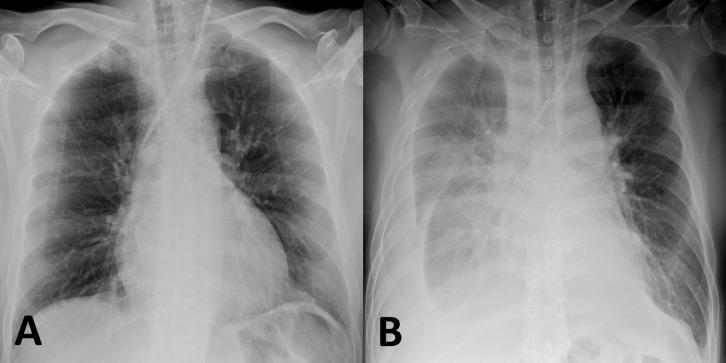

Delayed vascular injury (DVI) with a hemodialysis catheter is a rare but potentially life-threatening complication. However, the appropriate treatment for DVI has not yet been established. A 44-year-old man underwent placement of a hemodialysis catheter via the left internal jugular vein, and the first leukapheresis procedure was performed without complications. However, 3 days after the insertion of the hemodialysis catheter, the patient developed sudden dyspnea. Chest radiographs and contrast-enhanced computed tomography revealed that the catheter tip had migrated and was located outside the left brachiocephalic vein. DVI with catheter migration was diagnosed. To perform safe and reliable hemostasis, we successfully performed transvenous balloon-assisted tract embolization with n-butyl cyanoacrylate and the catheter was removed. To our knowledge, there has been no previous report of the treatment of balloon-assisted tract embolization with n-butyl cyanoacrylate for DVI caused by a hemodialysis catheter. Our treatment approach may be safe and effective for DVI.

血液透析导管相关的迟发性血管损伤(DVI)是一种罕见但可能危及生命的并发症。然而,针对DVI的恰当治疗方法尚未确立。一名44岁男性经左颈内静脉置入血液透析导管,首次白细胞分离术顺利进行,未出现并发症。然而,在血液透析导管插入3天后,患者突然出现呼吸困难。胸部X线片和增强计算机断层扫描显示导管尖端移位,位于左头臂静脉外。诊断为伴有导管移位的DVI。为实现安全可靠的止血,我们成功地用正丁基氰基丙烯酸酯进行了经静脉球囊辅助通道栓塞,并移除了导管。据我们所知,此前尚无关于用正丁基氰基丙烯酸酯进行球囊辅助通道栓塞治疗血液透析导管所致DVI的报道。我们的治疗方法可能对DVI安全有效。